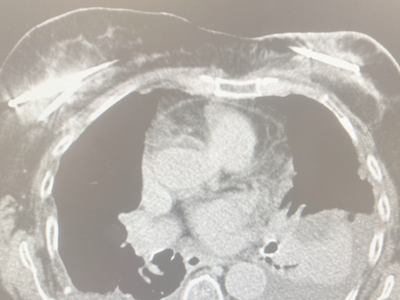

El cáncer de mama es uno de los tumores más frecuentes en la mujer. En los últimos años, el tratamiento ha evolucionado hacia opciones cada vez más conservadoras, con el objetivo de reducir la agresividad de los procedimientos sin comprometer la eficacia. En este contexto, la crioablación es una técnica de radiología intervencionista que permite tratar determinados tumores mamarios de forma mínimamente invasiva, sin necesidad de cirugía abierta.